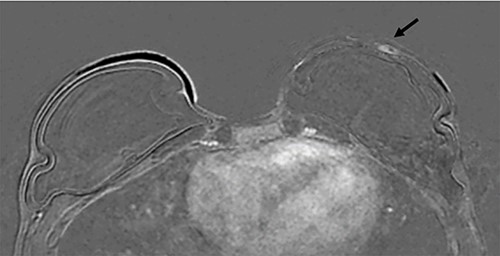

Three months postoperatively, the patient presented to the breast clinic with a nodule on the lower part of her left reconstructed breast deep to her (wide excision) scar. Ultrasound revealed an indeterminate nodule with a bright echoic centre. Differentials included the unabsorbed knot of an internal suture or possible local recurrence. Dynamic contrast breast MRI, however, did not demonstrate any abnormal enhancement. Ultrasound undertaken along with the operating surgeon demonstrated the patch of ADM inserted at the time of initial surgery as a thickening, with three identical regularly placed nodules measuring 3–5 mm corresponding to PDS sutures (Fig. 4), thus avoiding unnecessary surgery. Four months post-operatively, the nodule was no longer palpable.

(A) Magnified ultrasound image identified a 5 mm hypoechoic focus of thickening within the capsule (black arrow and area between the cursers) with two parallel lines centrally within the focus which represents the suture (white arrow). (B). The ultrasound demonstrates the equally placed sutures identified as small white parallel lines (arrows) across the ADM.